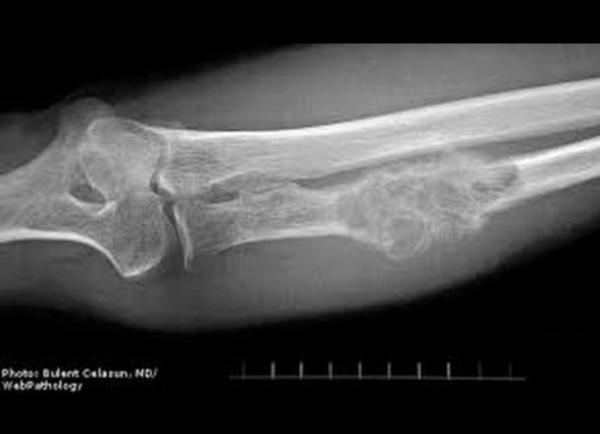

Waspada kanker tulang! Nyeri yang dianggap sepele bisa jadi ancaman serius jika terlambat ditangani. (Foto: ist)

PANGANDARAN, iNewsPangandaran.id -   Penyakit mematikan kerap datang tanpa tanda. Salah satunya Kanker Tulang yang dikenal “senyap” di awal kemunculannya. Tak sedikit korban baru tersadar saat kondisinya sudah parah.